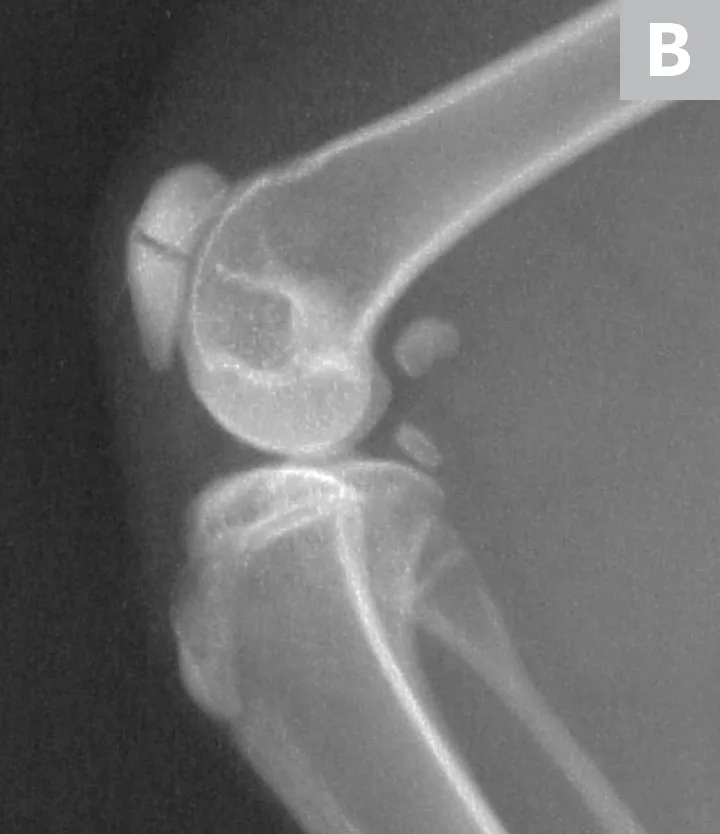

Serial radiographs of the pelvic limbs were taken periodically to monitor progression of the patellar fractures. Comparative orthopedic radiographs (Figure 3) 2 and 8 years after initial presentation revealed persistence of patellar fractures, with fragmentation, progressive sclerosis, and osteophytosis of the left patella.

Radiographs of the patellar fractures taken 2 years (A, left stifle; B, right stifle) and 8 years (C, left stifle; D, right stifle) after initial presentation. Progressive fragmentation and osteophytosis of the left patella and displacement of the right patellar fragments can be seen.